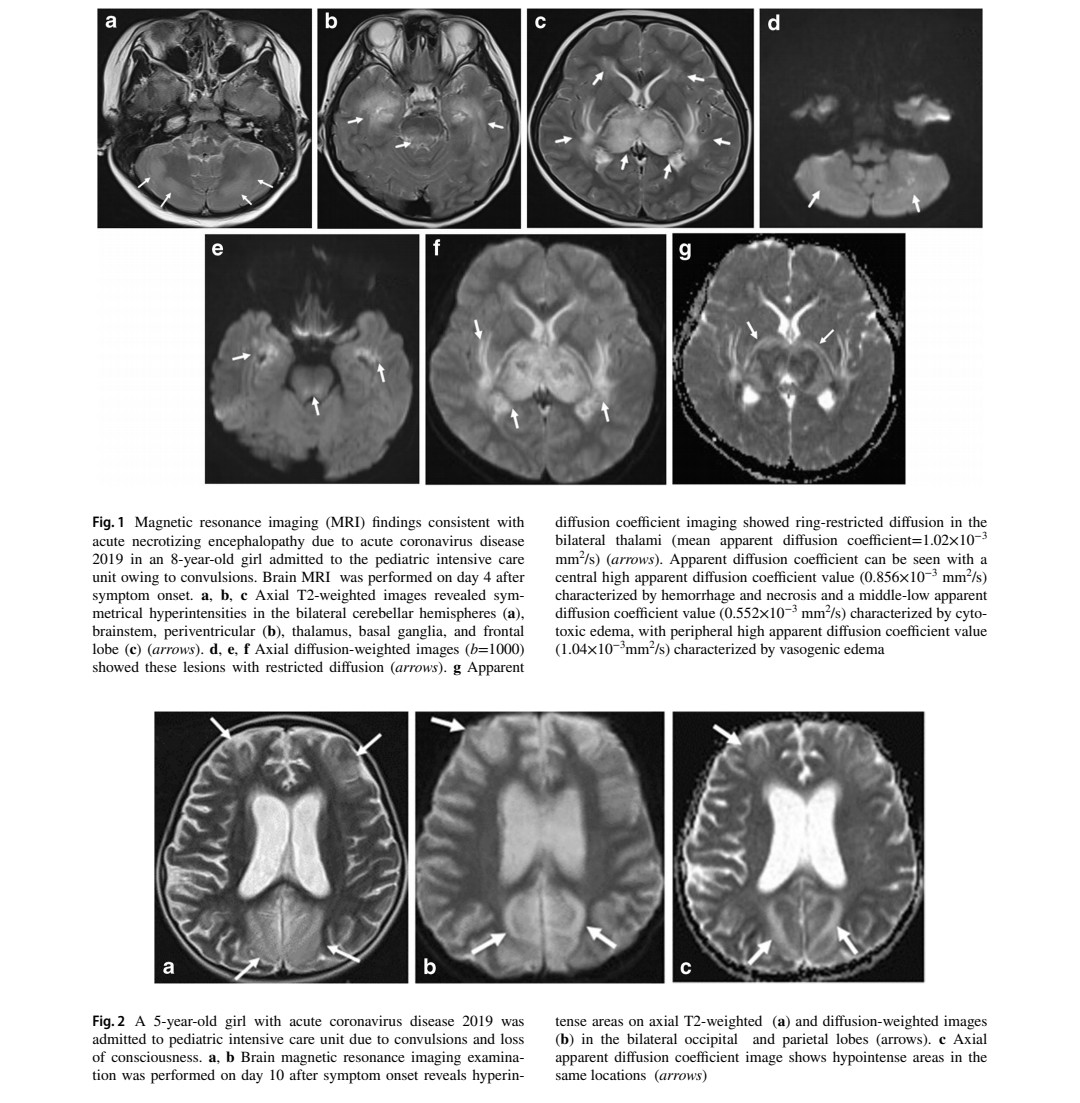

๐˜ฝ๐™ง๐™–๐™ž๐™ฃ ๐™ข๐™–๐™œ๐™ฃ๐™š๐™ฉ๐™ž๐™˜ ๐™ง๐™š๐™จ๐™ค๐™ฃ๐™–๐™ฃ๐™˜๐™š ๐™ž๐™ข๐™–๐™œ๐™ž๐™ฃ๐™œ ๐™›๐™ž๐™ฃ๐™™๐™ž๐™ฃ๐™œ๐™จ ๐™ž๐™ฃ ๐™˜๐™๐™ž๐™ก๐™™๐™ง๐™š๐™ฃ ๐™ฌ๐™ž๐™ฉ๐™ ๐™ฃ๐™š๐™ช๐™ง๐™ค๐™ก๐™ค๐™œ๐™ž๐™˜๐™–๐™ก ๐™˜๐™ค๐™ข๐™ฅ๐™ก๐™ž๐™˜๐™–๐™ฉ๐™ž๐™ค๐™ฃ๐™จ ๐™ค๐™› ๐˜พ๐™Š๐™‘๐™„๐˜ฟ-19 (๐™Š๐™ข๐™ž๐™˜๐™ง๐™ค๐™ฃ ๐™ซ๐™–๐™ง๐™ž๐™–๐™ฃ๐™ฉ) ๐Ÿ˜จ

Image

2) This study analyzed brain MRI findings in 102 pediatric patients infected with Omicron who were admitted to PICUs with neurological complications. The average age was 5.8 years and most patients were male. Common symptoms included fever, convulsions and altered consciousness. Image

3) MRI was performed 1-12 days after symptom onset in 93 patients. Abnormal neuroimaging findings were seen in 74% of cases. The most common finding was acute necrotizing encephalopathy seen in 48% of cases with abnormal MRI. This involved lesions in the thalamus, brainstem ... Image